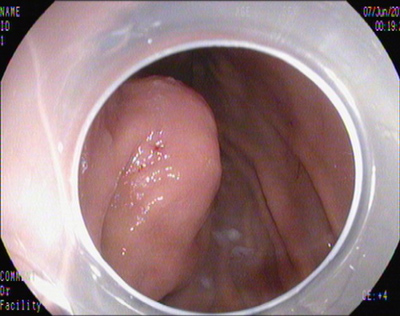

胃腔内瘤体

2014年7月4日,田俊斌医师施行全身麻醉,李雪荣、左爱丽护师等为手术护士,邹百仓主治医师、张莉主治医师施行EFTR手术。胃镜下见胃底体交界前壁见巨大粘膜下肿瘤,暴露于胃腔的瘤体大小约3.0×4.0cm,表面光滑,中央凹陷。粘膜膜下注射后,环形切开瘤体周围粘膜,剥离瘤体周围粘膜下层,中央与肌层紧密连接,并向腔外生长,全层切开瘤体周围肌层,完整切除瘤体,可见腹腔脏器及网膜组织,钛夹尼龙圈荷包缝合切口,尼龙圈脱落,后用钛夹夹闭缝合切口,创面无渗血。由于标本较大坚硬无法完整一次取出,用圈套器将瘤体分切成5块,分块取出,拼凑复原瘤体形态,测量大小4.0×5.0cm。术后4天胃镜复查:胃壁切口溃疡形成,无出血及穿孔,嘱患者进食流质饮食。病理结果:胃底间质瘤,中、低度恶性风险,向神经纤维瘤发展。术后1周出院。